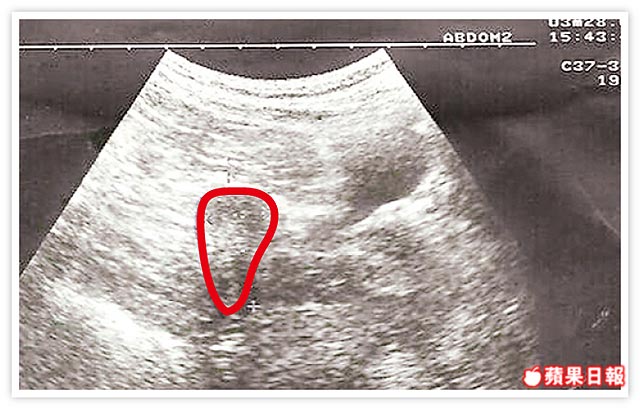

女子幼時放療卵巢瘤,子宮連帶萎縮至直徑僅一點七公分(圖中紅圈處),如小桃子。蔡鋒博醫師提供

蔡鋒博說,女子自述二十三年前罹患卵巢瘤,醫師評估不適開刀,照鈷六十放療讓腫瘤消失,但卵巢及子宮隨之萎縮,且因子宮無卵巢分泌的動情激素滋潤,變得又硬又小。蔡鋒博形容,成年女性子宮直徑約七公分,大小如蘋果,女子的子宮左右寬度和上下長度,各僅一點七和三點六公分,僅約桃子大,子宮鏡檢查也看到子宮壁有放療後的白色疤痕,子宮變得硬梆梆。